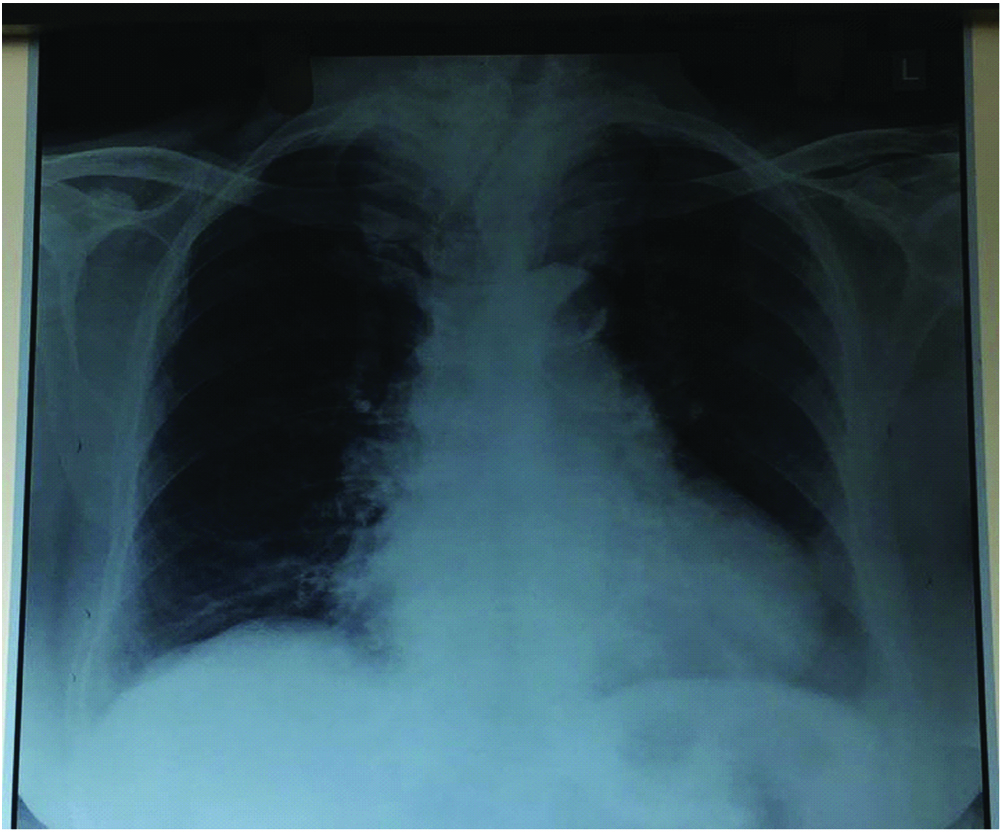

On examination, vitals were stable with PR-70/min, BP-140/90 mm Hg, SpO2 of 100%. Baseline investigations were within normal limits with Hb-10.9 mg/dL and low calcium 7.3 mg/dL. Electrocardiogram (ECG) showed complete right bundle branch block with normal Echocardiography (ECHO) study. Thyroid profile showed low TSH-0.011 IU/mL with normal T3, T4 values. Chest radiograph showed narrowed and deviated trachea with widening of superior mediastinum [Table/Fig-2]. Computed Tomography (CT) neck showed thyroid gland with heterogeneous enhancement with areas of necrosis and calcifications within the gland. The right lobe measured 10.8x5.5 cm and left lobe measured 8.9x5 cm. Inferiorly left lobe was seen extending into retrosternal area. Superiorly, the right lobe was extending upto C2 vertebra. Medially the lesion was compressing trachea with significant narrowing of air column with subglottic diameter of 6.2 mm [Table/Fig-3]. Upper trachea was displaced to left side. The lesion was abutting thyroid, cricoid cartilages and inferiorly arch of aorta. Fine Needle Aspiration Cytology (FNAC) report was consistent with benign follicular nodule.

Figure showing AP view chest X-ray of narrowed and deviated trachea.